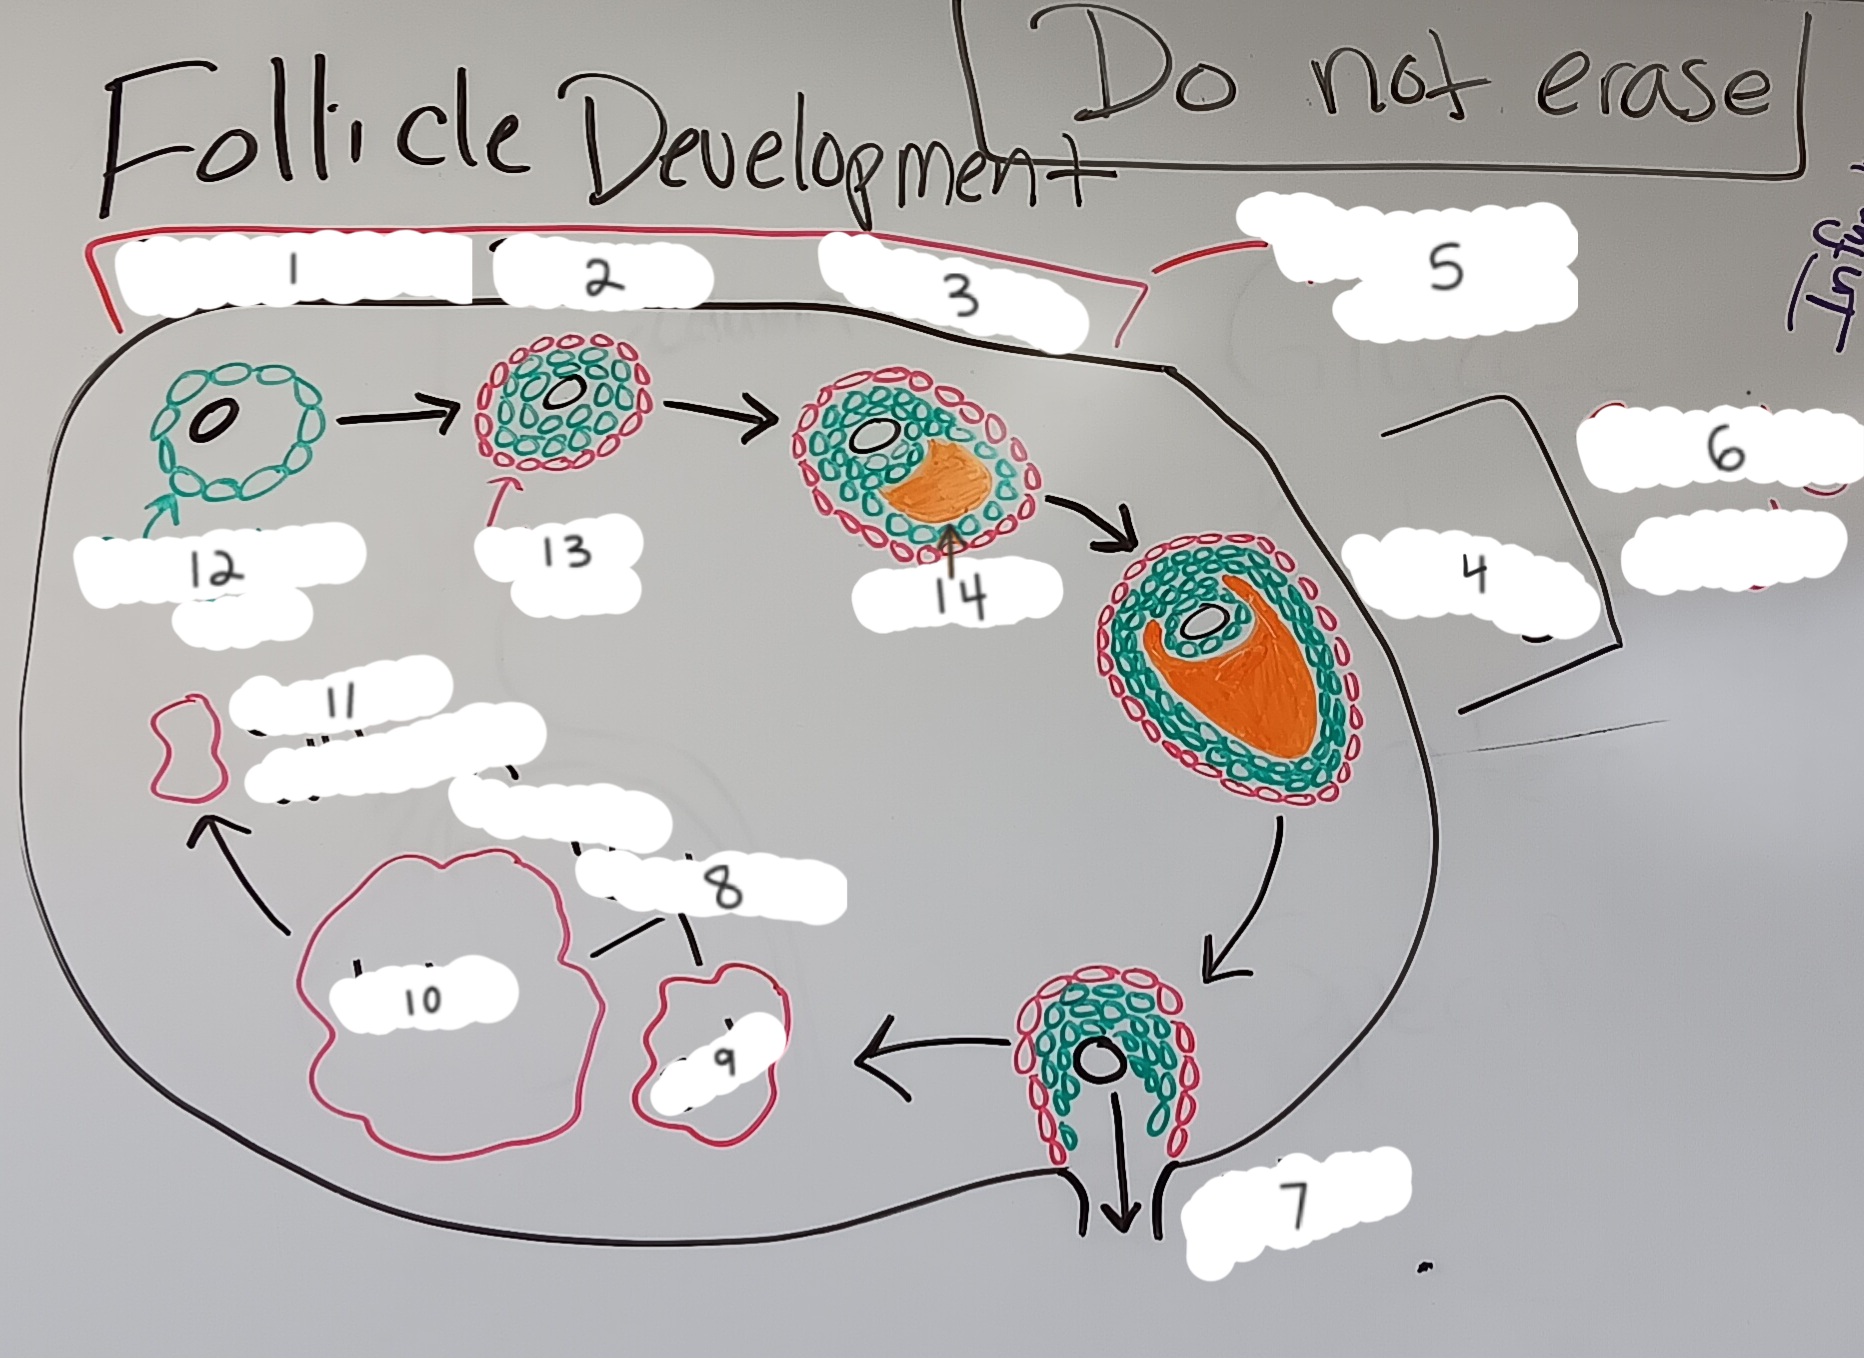

Oocyte

6 (the whole structure)

Primary oocyte

5

Secondary oocyte

6

Granulosa cell

7

Primordial follicle

1

Primordial follicle

Primordial follicle

1

Primary follicle

2

Primary follicle

Primary follicle

2

Secondary follicle

3

Secondary follicle

Secondary follicle

3

Tertiary follicle

4

Tertiary follicle

4

Mature follicle

5

Mature follicle

Mature follicle

7

Antrum

10

Zona pellucida

9

Theca folliculi

8

Corona radiata

Corpus luteum

Corpus luteum

Corpus albicans

Corpus albicans

corpus luteum

8

early corpus luteum

9

late corpus luteum

10

corpus albicans

11

granulosa cells

12

theca cells

13

antrum

14